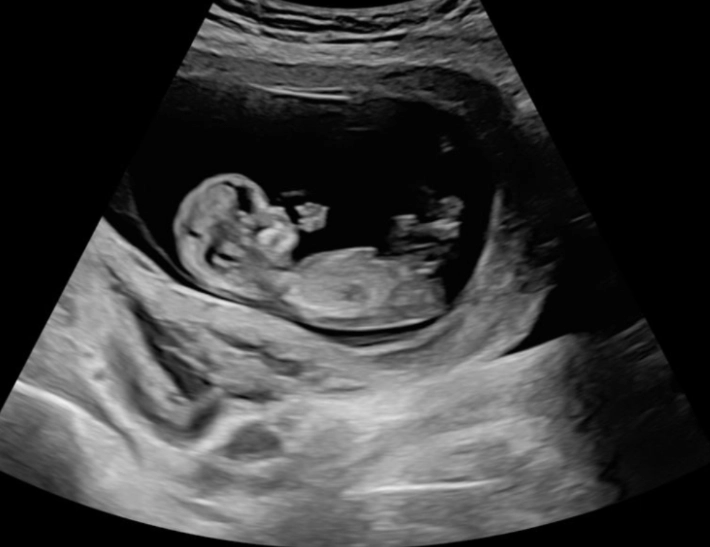

At 12 weeks pregnant, your uterus has grown from the size of a pear to about the size of a large grapefruit. The key detail? It’s still tucked neatly within your pelvic bone. For most first-time moms, it hasn’t risen above the pubic bone yet. That official "popping" moment usually happens between 16 and 20 weeks.